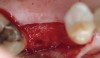

The patient was a 66-year-old man who required removal of the three mandibular right molars due to rampant caries and attachment loss. Following flap reflection and extractions, the sockets were debrided with both ultrasonic and manual instrumentation (Figure 10). The sockets of the first and second molars were augmented with rhBMP-2/ACS. The site of the third molar was obturated with a noncrosslinked, collagen plug for hemostatic purposes only.

Figure 10  Extraction and debridement of tooth Nos. 30 through 32.

Figure 10